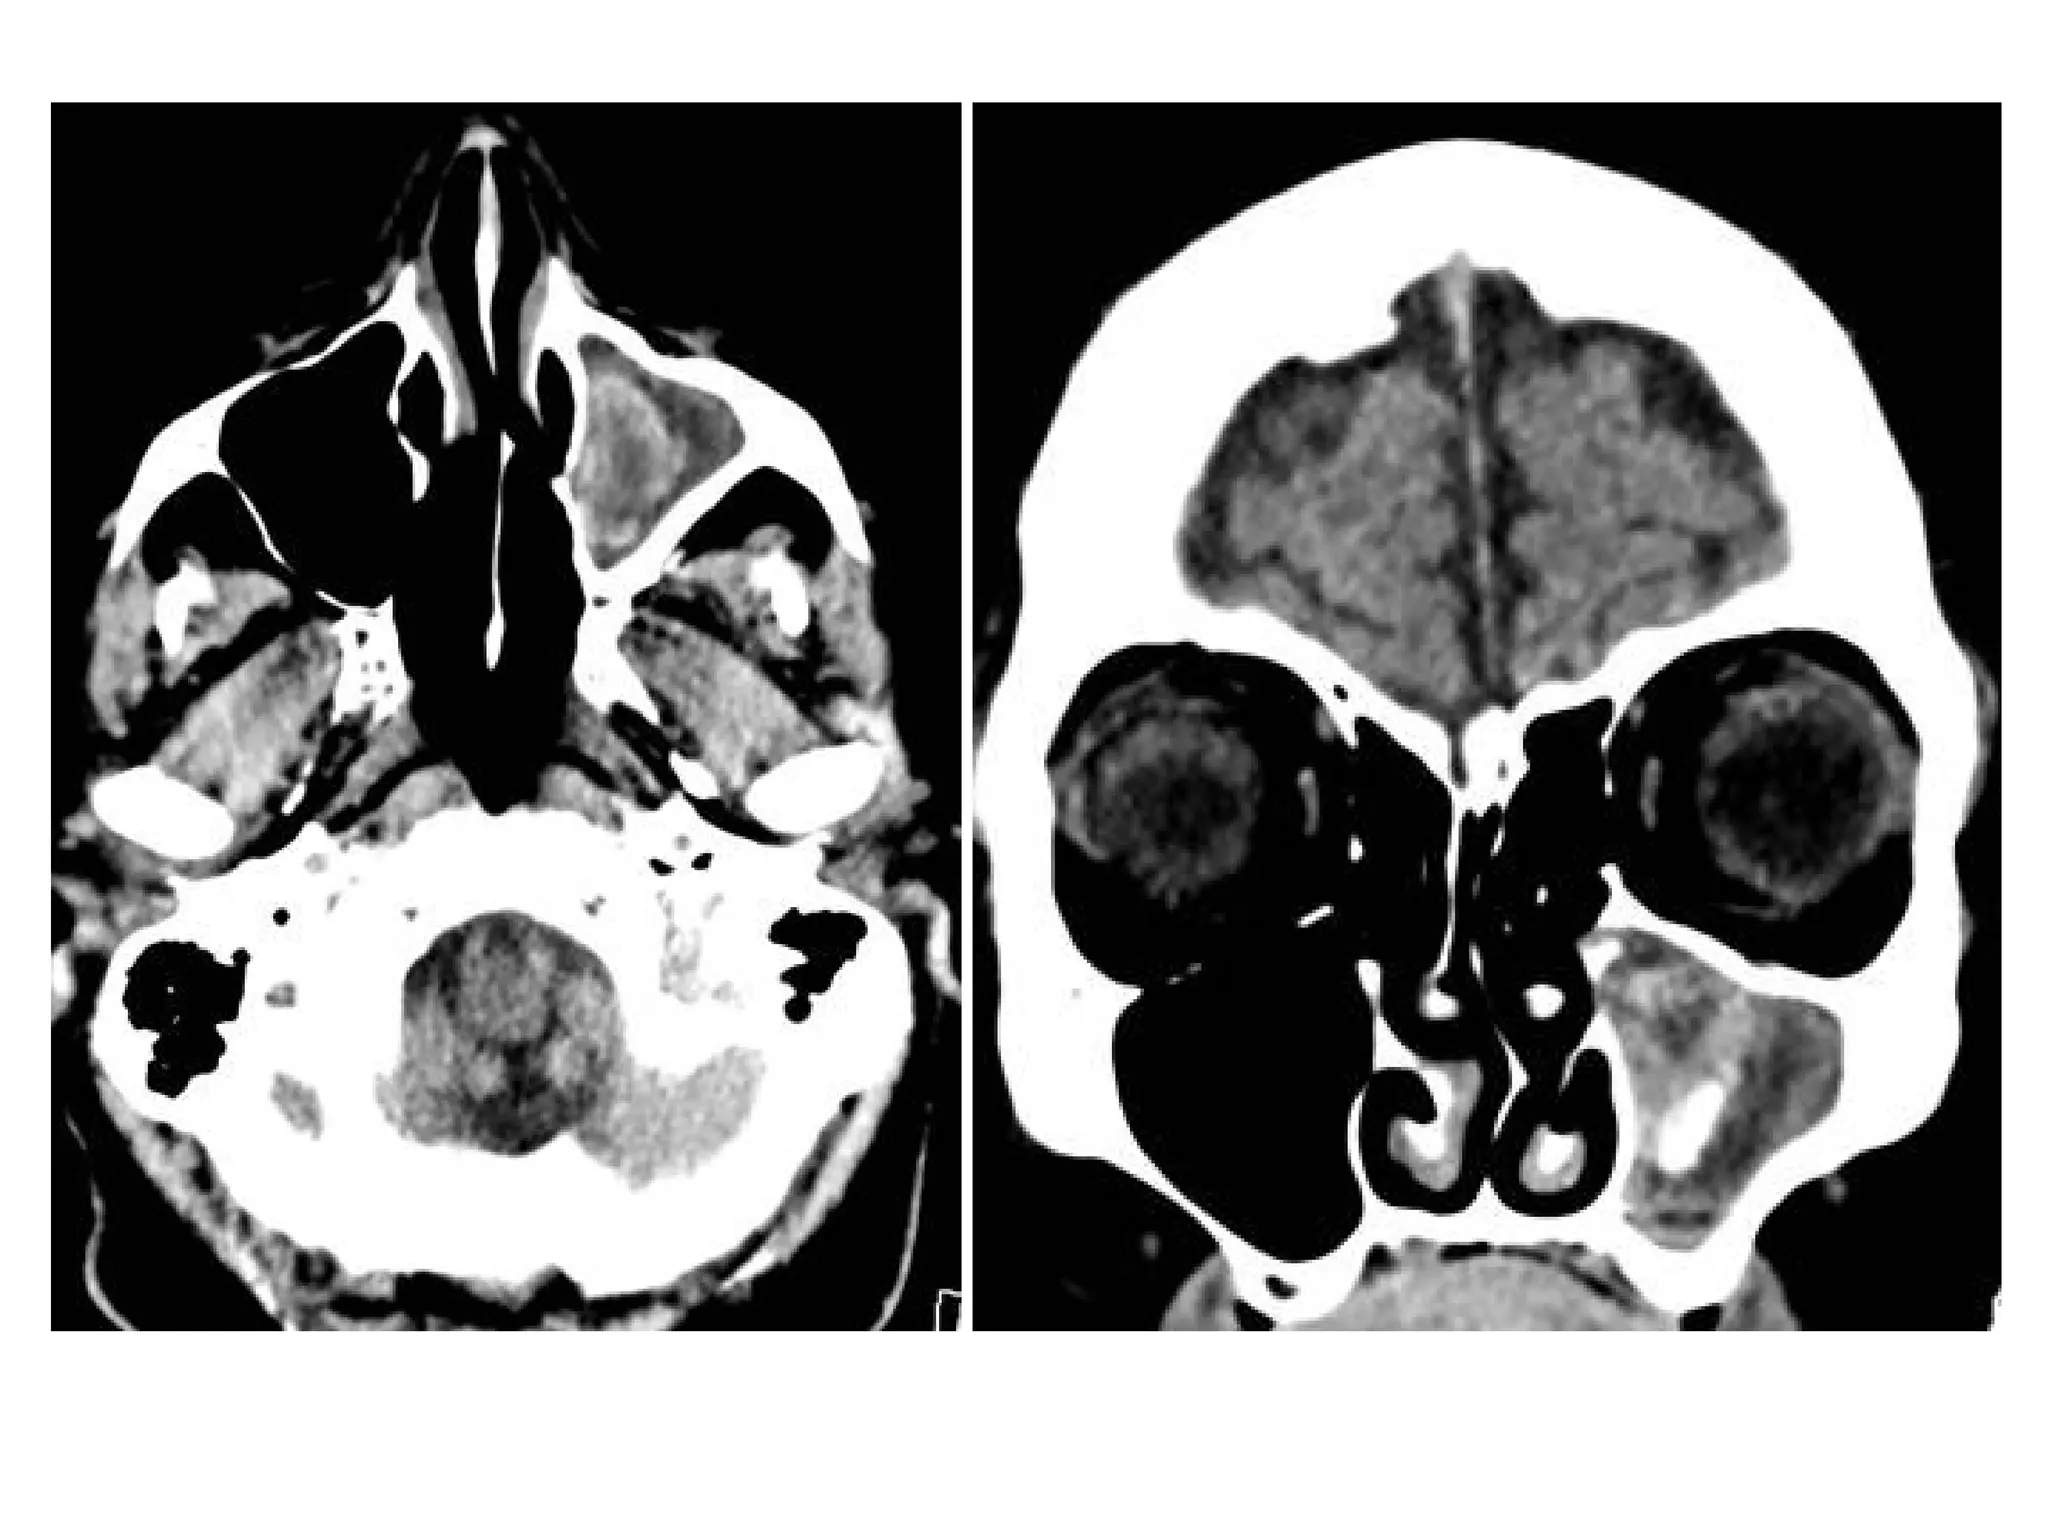

Sinusitis with orbital subperiosteal abscess